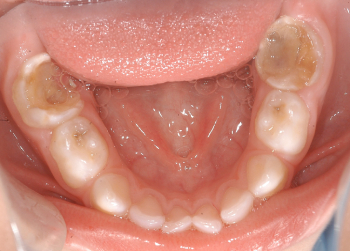

Antes: